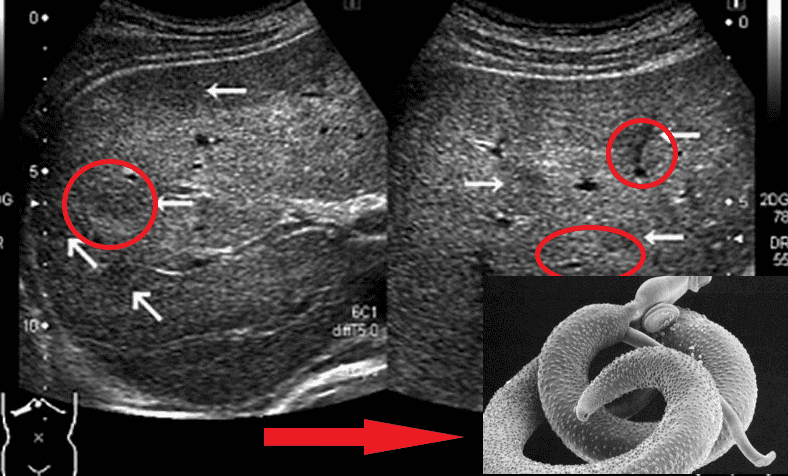

Представниками гельмінтів, що вражають життєво важливі органи, є Taenia solium, ехінокок (Echinococcus granulosus), трихінела (Trichinella spiralis). Ехінокок являє собою личинкову стадію гельмінта з роду Echinococcus. І це далеко не всі види паразитів, здатні убити людину.

"Ходи" паразитів у просвіті кишечника